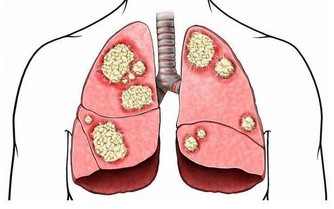

3、影響消化系統功能

經常久坐不動,還會降低人體的胃腸動力,減少消化液的分泌,這不利於人體對食物的消化吸收,容易出現食慾不振、消化不良、腹脹、便秘等現象,可能會引起胃潰瘍、十二指腸潰瘍等疾病,嚴重的還會導致結腸癌。